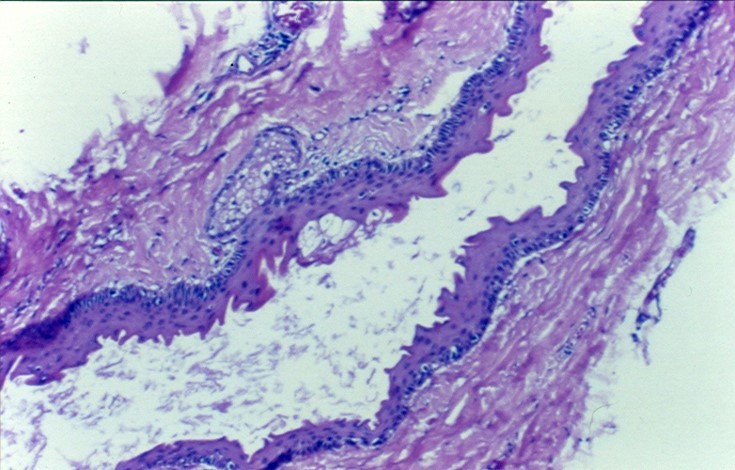

What disease process is pictured below?

Fibroepithelial polyp

What may be associated with fibroepithelial polyps?